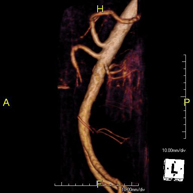

- Abdominal aorta MRI angiography

A non-invasive diagnostic test that involves studying the abdominal aorta, obtaining high-definition anatomical images using an electromagnetic field and radio waves (with transmitter and receiver). The use of paramagnetic contrast (gadolinium) is essential. However, it is a radiation-free procedure. The quality of the images allows for 2D and 3D reconstructions. It is indicated in patients with vascular disease (atherosclerosis), aneurysm studies, pre-surgical studies of lesions adjacent to the abdominal aorta as a vascular ‘map’, etc.